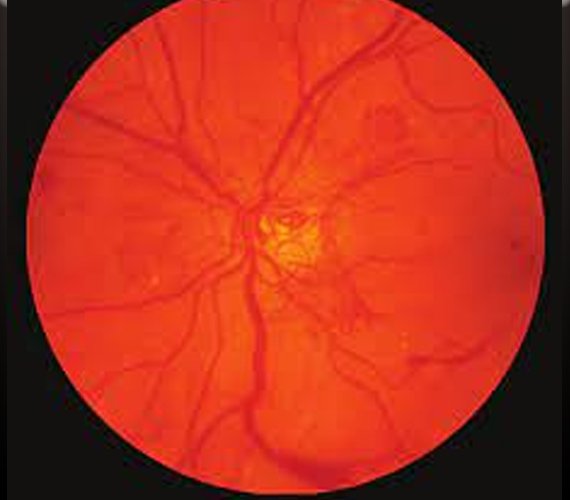

Diabetic retinopathy is a serious complication of diabetes that affects the eyes. It occurs when high blood sugar levels damage the blood vessels in the retina, leading to vision problems and potentially blindness if left untreated. Managing diabetic retinopathy involves a combination of medical interventions, lifestyle changes, and regular eye screenings to prevent further damage and preserve vision.

One of the primary approaches to managing diabetic retinopathy is controlling blood sugar levels. This typically involves a combination of diet, exercise, and medication as prescribed by a healthcare professional. By maintaining tight control of blood sugar levels, the progression of diabetic retinopathy can be slowed or even halted in some cases.

Another crucial aspect of managing diabetic retinopathy is controlling blood

pressure and cholesterol levels. High blood pressure and cholesterol can exacerbate the damage to blood vessels in the retina, so medications and lifestyle modifications may be recommended to keep these levels within a healthy range.

Regular eye examinations are essential for monitoring the progression of diabetic retinopathy and detecting any changes early on. These exams, which may include dilated eye exams and imaging tests, allow eye care professionals to assess the health of the retina and determine the appropriate course of action.

In some cases, treatment may be necessary to prevent vision loss or improve vision in individuals with diabetic retinopathy. One common treatment option is laser therapy, which involves using a laser to seal off leaking blood vessels or shrink abnormal blood vessels in the retina. This can help reduce swelling and preserve vision.

In more advanced cases of diabetic retinopathy, injections of anti-VEGF medications may be recommended. These medications help reduce the growth of abnormal blood vessels and can slow the progression of the disease.

In severe cases where vision loss has occurred, surgical procedures such as vitrectomy may be necessary to remove blood or scar tissue from the eye and improve vision.